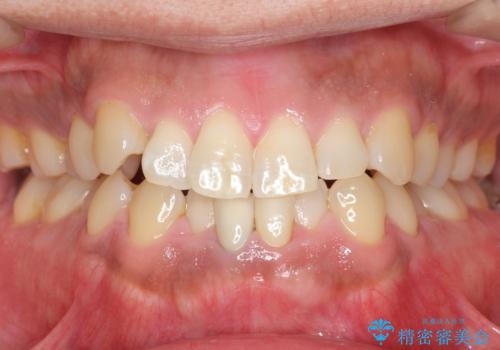

神経が死んでいる歯の根管治療を行った後、セラミッククラウンによる補綴治療を行いました。

比較的短期間(2ヶ月、来院回数:5回)で治療が終わったこと、また自然な仕上がりと使用感にご満足頂けました。

~被せ物の種類~

ジルコニアクラウン スタンダード